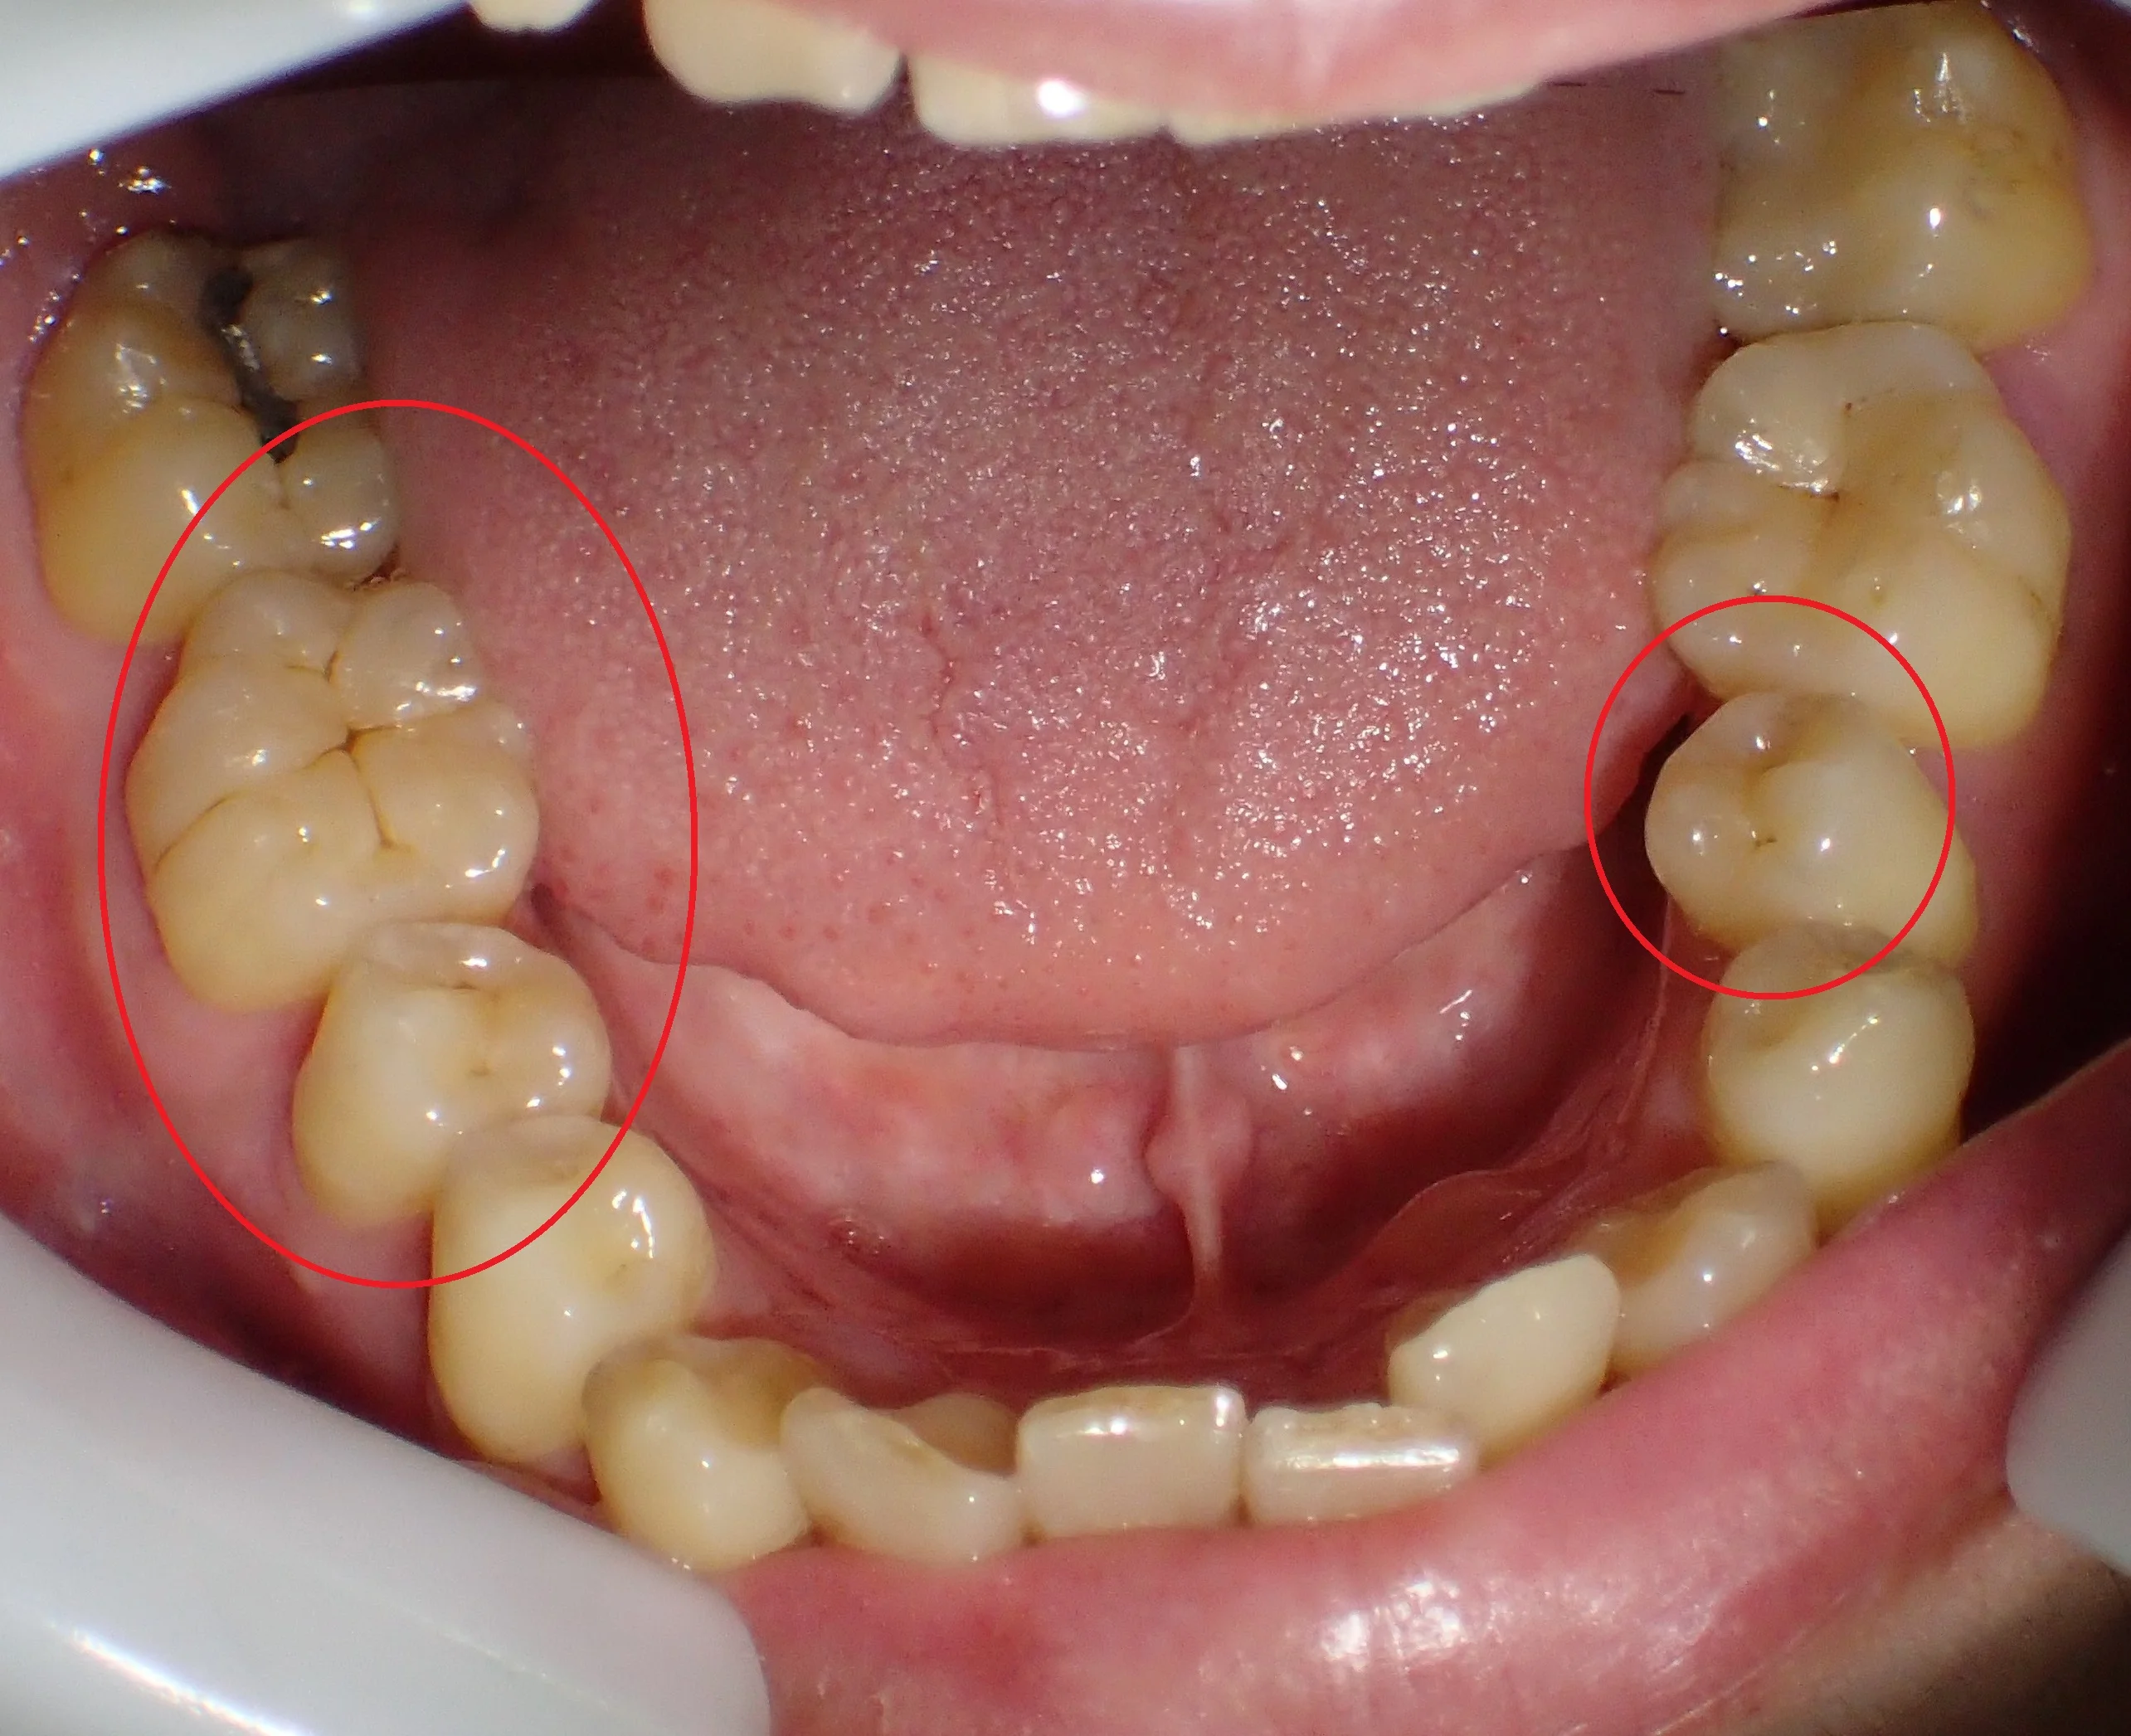

治療した箇所は、

・右下5,6

・左下5

治療した部位は全て元々詰めていたメタルインレーが再び虫歯になってしまった状態でした。

幸いあまり大きくは削られてはいなかったので、全てをダイレクトボンディングで治療することが出来ました。

右下7はアマルガムという金属が入っていますが、別にそこは虫歯にはっていなかったです。

なので、患者さんの同意の下、治療はせずにそのままにしています。

ステイニングを行って、歯の溝の部分に色を付けると歯に立体感が出るので、急激に天然の歯っぽくなりますよね!

ちなみに、この方、右下6を一番最初に治させて頂いたのですが・・・

もう少しステイニングを弱めにしてほしいとの要望があり、他の箇所は控えめなステイニングにしました。

全ての治療を終え、患者さん本人には非常に喜んでもらえました。